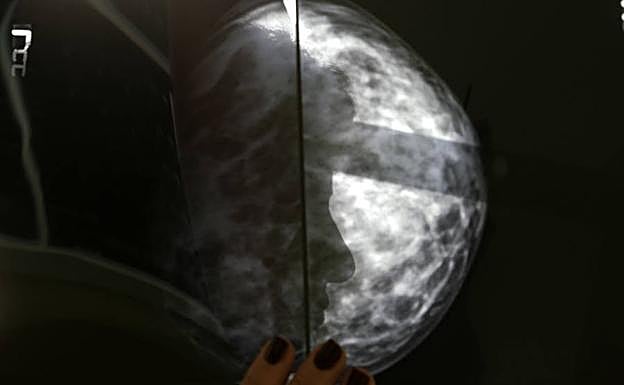

Mamografía. Reuters

Para ello, el equipo de investigación han revisado un total de 90.000 mamografías de detección de alta resolución de aproximadamente 40.000 mujeres para entrenar, validar y probar el modelo de aprendizaje profundo. «Hay mucha más información en una mamografía que solo las cuatro categorías de densidad mamaria», señala Adam Yala, autor principal del estudio.

La densidad mamaria es un factor de riesgo independiente para el cáncer de mama que se ha agregado a algunos modelos para mejorar la evaluación de riesgos. El entrenamiento ha permitido a esta inteligencia artificial reconocer los sutiles patrones del tejido mamario que son precursores de su malignización.